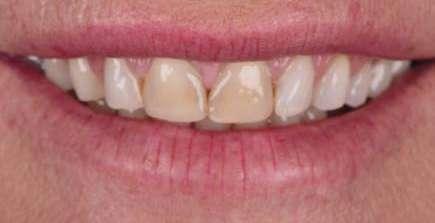

Presentación del caso clínico

A continuación, presentamos el caso clínico de una paciente con unos dientes mal posicionados y con una coloración acentuada sobre todo a nivel de los centrales que además presentaban extensas restauraciones antiguas de composite en interproximal cerrando diastemas que originalmente presentaba la paciente. Estos dientes necesitarán tener una preparación un poco más subgingival y también removido previamente todo el composite antiguo con el objetivo de camuflar este cambio de color y evitar zonas visiblemente no estéticas.

Además, lo combinaremos con unas carillas inyectadas inferiores también planificadas digitalmente y sin tallado, para crear una armonía y equilibrio con la parte superior.

1 Inicio.

Como podemos observar la paciente tenía un sustrato muy desfavorable, con un color aproximado de A3,5 Vita.

Mockup.

En la arcada superior por el contrario se decidió poner unas carillas de disilicato para poder cubrir las expectativas de la paciente y ajustar el color al que ella deseaba, bajando casi en 5 tonos el color final. Se planificaron preparaciones digitales conservadoras.

Como se puede observar en la imagen comparativa, la planificación se reproduce de una forma fiel a lo que se había planificado y aceptado por la paciente. Por tanto, no es una técnica susceptible al operador, que se realiza controlando mucho mejor los tiempos y los resultados obtenidos.

15 16 17 18 19 20 21 Preparación. Prueba en seco. Ajuste. Final.

¡Obteniendo un caso espectacular en apenas un par de citas!

Y pudiendo, gracias al uso de este tipo de tecnología, controlar las expectativas y resultados desde el principio hasta el final del caso.

El momento más esperado es el de la celebración por parte de la paciente y del equipo, al conseguir el resultado exacto que se había prometido al principio por medio del mockup y que determinará la confianza que nuestros pacientes depositarán en nosotros cuando les planteemos este tipo de tratamientos. 